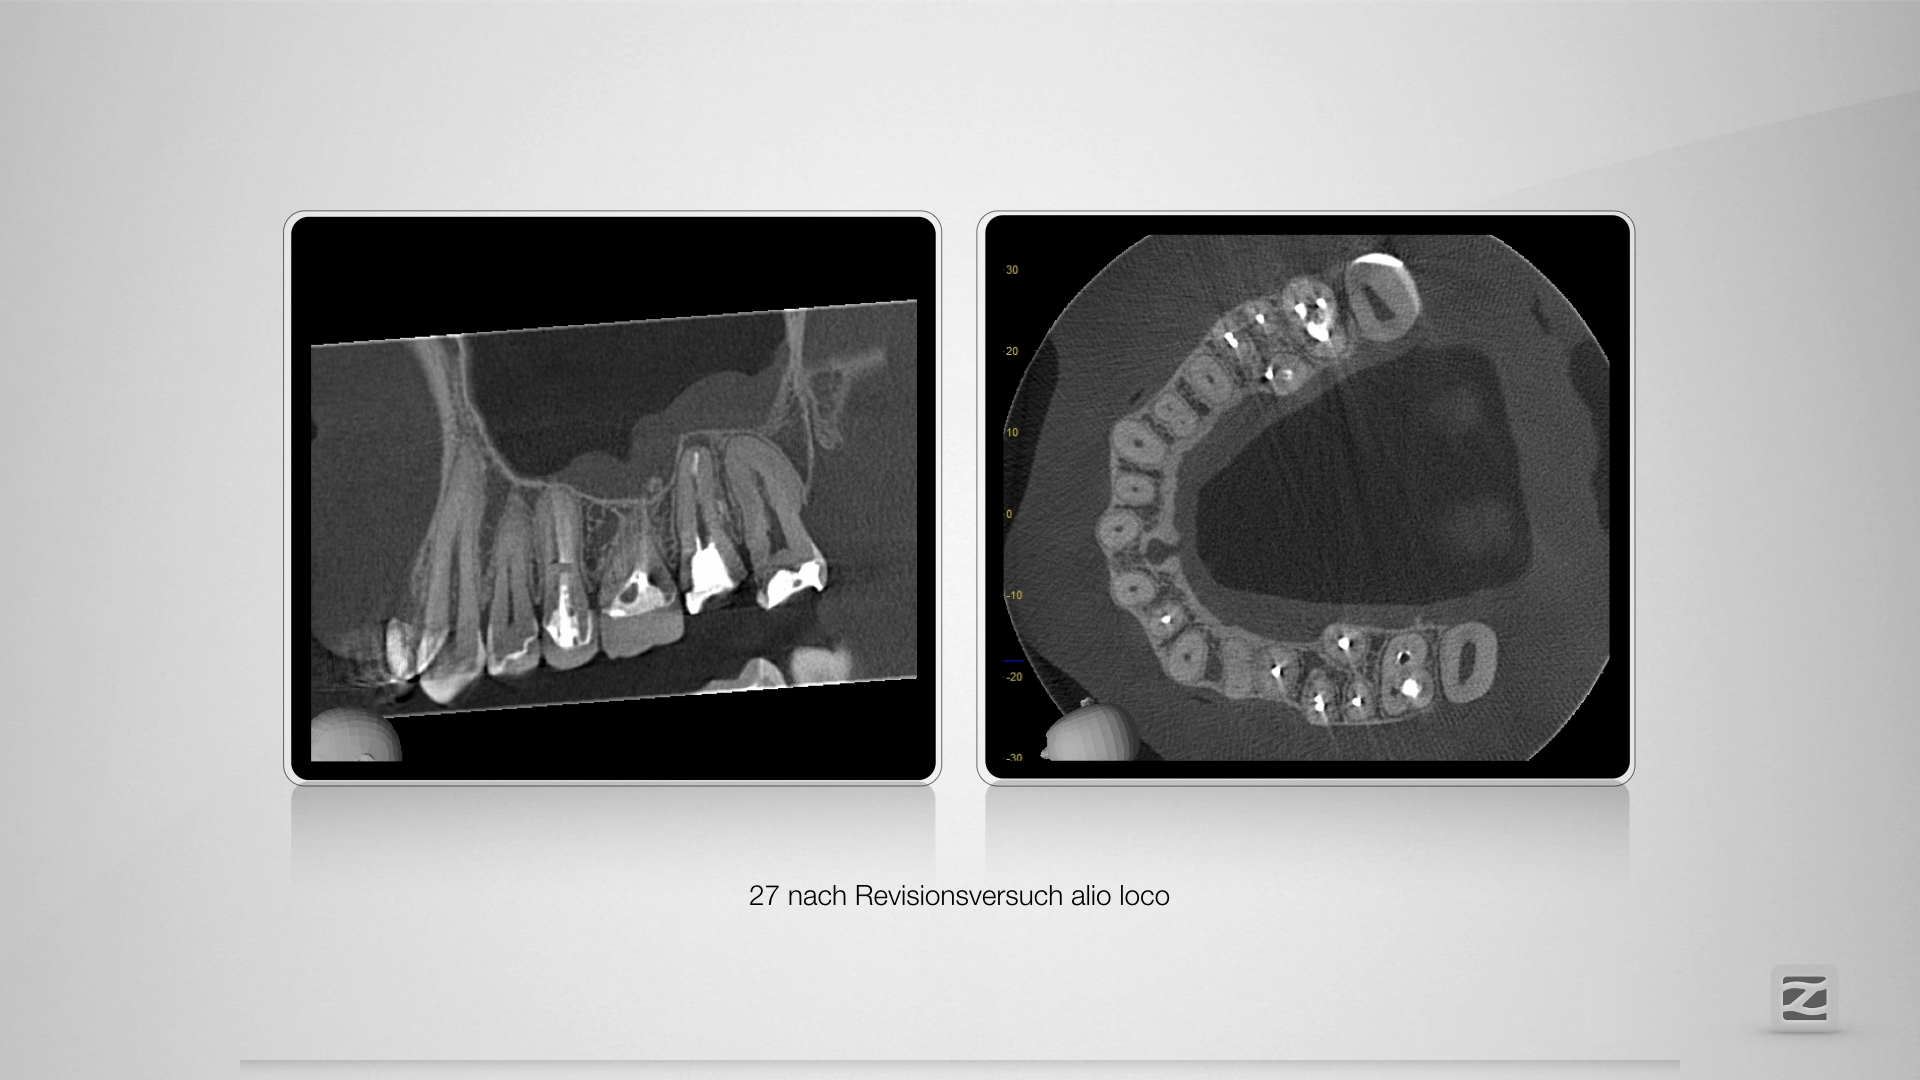

Fast getroffen ist auch vorbei!